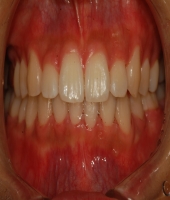

| ● 진료과목 : [치아교정] (교정)비발치 총생 치료

| ● 내용 : 심한 총생에서도 발치 없이 교정치료 |